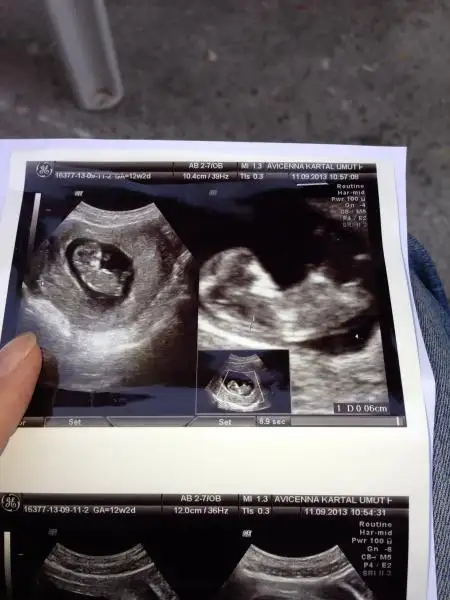

rica etsem benim bebeğimede bakabilirmisiniz lütfennn :)Eki Görüntüle 811667 Eki Görüntüle 811668

tam yükleyemedim galiba anlayamazsanız tekrar yüklerim